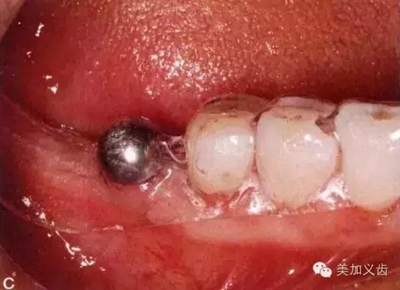

如何通過曲面斷層片測量出相對準(zhǔn)確的數(shù)據(jù)?告訴大家一個很實用的方法,就是利用小剛球作為參照。

將小剛球放到口內(nèi)時拍攝曲面斷層片,拍攝后得到的結(jié)果就是這個樣子的:

5.jpg

因為小剛球的直徑是固定的,通過測量片子上小剛球的直徑,就能算出曲面斷層片的放大率,然后就能算出真實的骨高度了,這是一個很不錯的方法。

拍片時怎么把小剛球固定在口內(nèi)?有的牙醫(yī)用紅蠟把它固定在鄰牙上,這是一種比較玩火的做法,一旦掉了怎么辦?重新拍?一旦患者把小剛球咽到肚子了怎么辦?讓患者賠你小鋼球?我一定是在開玩笑,呵呵,患者不讓你賠錢就不錯了。

別嫌麻煩,給患者術(shù)前取個模型,然后通過壓膜來制作放射導(dǎo)板,這樣小剛球就固定在導(dǎo)板里了,別說你的診所沒有壓膜機哈......